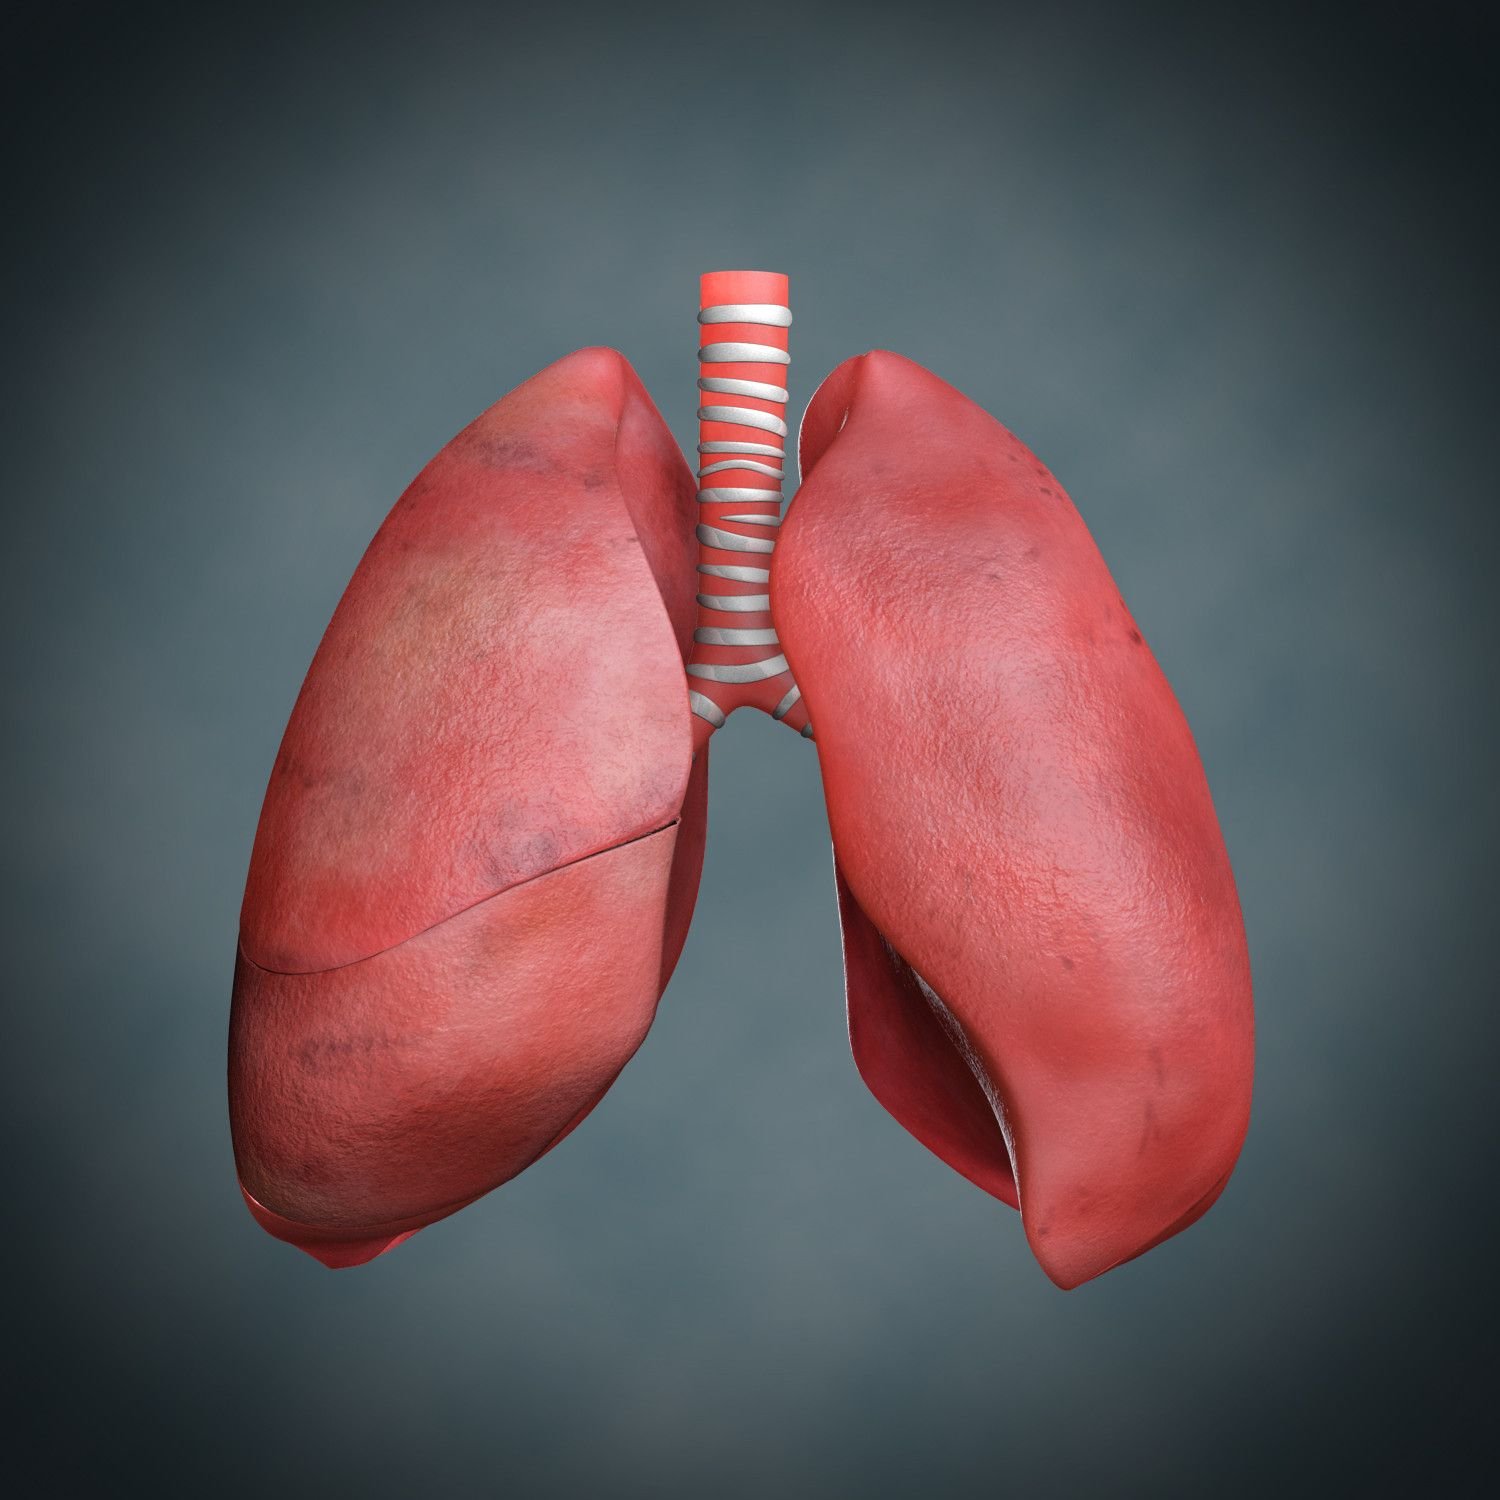

Здоровые Легкие Картинки

Здоровые Легкие Картинки 117 фото